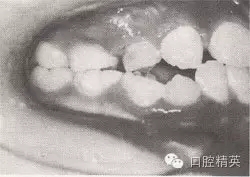

患者,女,10歲,替牙頜。磨牙近中關(guān)系。前牙反頜,下頜前突。下頜體稍長,下頜位置前移,上頜前頜骨區(qū)發(fā)育稍差。

診斷:安氏Ⅲ類前牙反猞,骨性Ⅲ類,毛氏Ⅱ¹。

矯治設(shè)計:面罩前牽引上頜,移下頜位置向后,抑制下頜生長??趦?nèi):全牙弓夾板,后牙平面頜墊式活動矯治器。矢狀關(guān)系調(diào)整后,去掉前牙區(qū)夾板,雙曲舌簧加力移切牙向唇向。

治療時間:2個月,上頜前移,下頜位置后移,切牙覆猞、覆蓋正常。

圖8-44 安氏Ⅲ類錯頜,混合牙列前牙反頜矯治前后面頜像

矯治前面相

矯治后面相